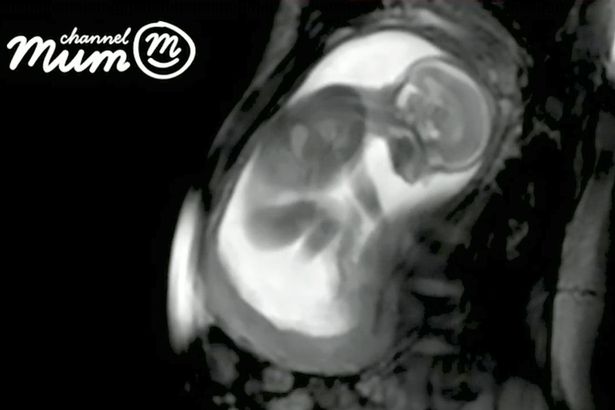

Image Credit: Channel Mum

In this newest video, an MRI ultra-sound, the living child is just 20 weeks old, the age pro-lifers want to protect unborn children from abortion. This is also the age abortion advocates don’t want protected, even though these unborn children can feel pain and are just as human and alive as you and I.

In the video we get to see the child in amazing detail through the use of MRI and ultra-sound technology. We get to watch as the child turns her head, kicks her legs, squirms around seeming to try and reposition or get comfortable in her small living space. She even stretches her legs. And, if you look closely, you will see this little child’s beating heart. Once you see a video like this, it is impossible to deny that this is a living human being.